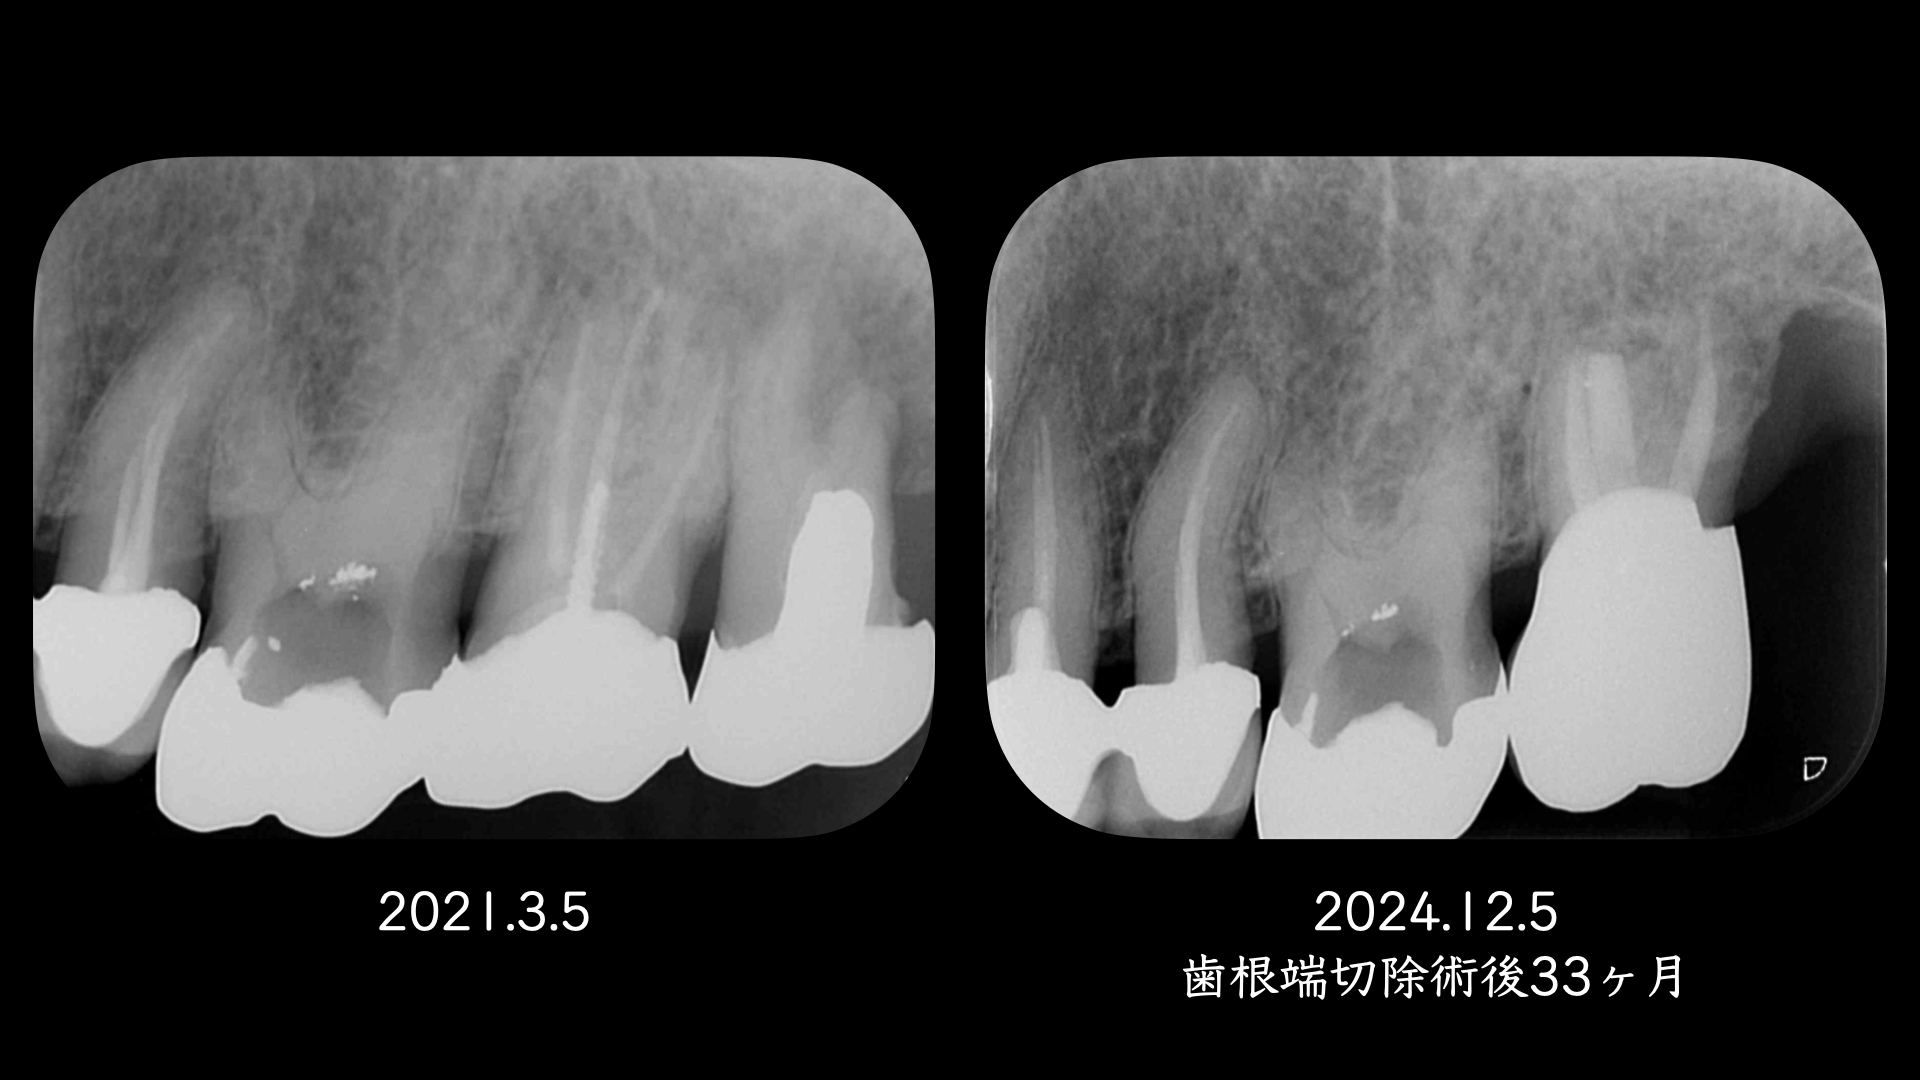

右の画像のCT上で根尖部にかなり大きな透過像があります。

術後、歯根は骨に囲まれるように治癒にしました。

このように非外科的な治療のみでは治癒に導けない場合は、外科的歯内療法で保存できる可能性があります。